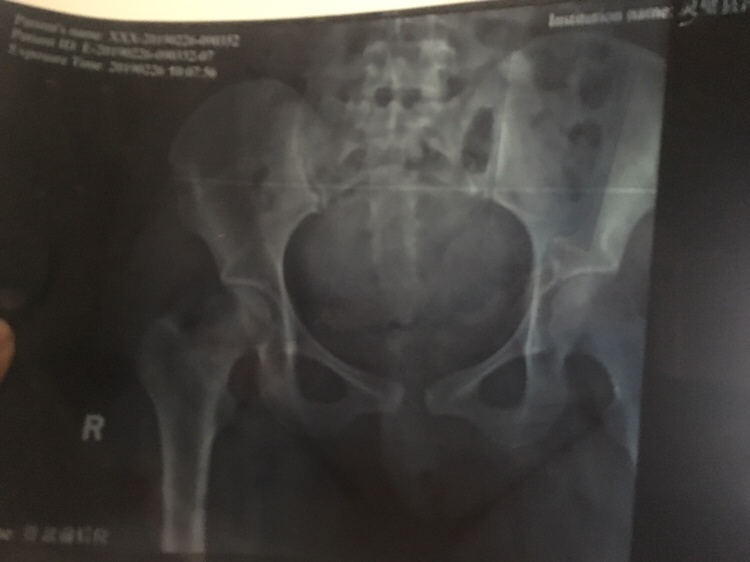

小。亦。宸[帖主]:我打算出月子再去拍个片子,然后就去做骨盆修复 希望有点效果 因为我这二胎 产后修复一定要去做了

??:对呀 三个月内做效果最好 我今天才去医院把钱交了

我产后也分离,但是没你那么严重,能走,但是下床的时候超级酸疼,现在快3个月了,基本上好了,还有一点酸